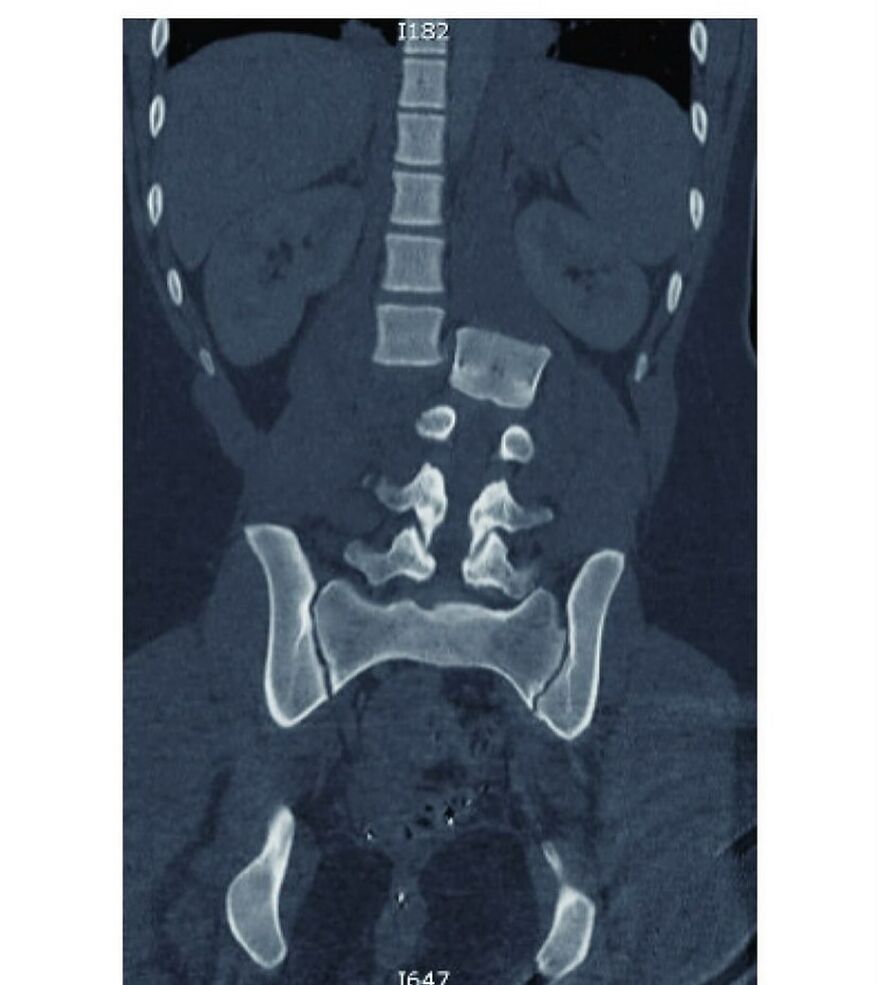

A 15-year-old boy has three extra vertebrae in his neck - a condition known as supernumerary vertebra along with congenital scoliosis - causing pain, stress on his nerves, and making it difficult for him to walk.